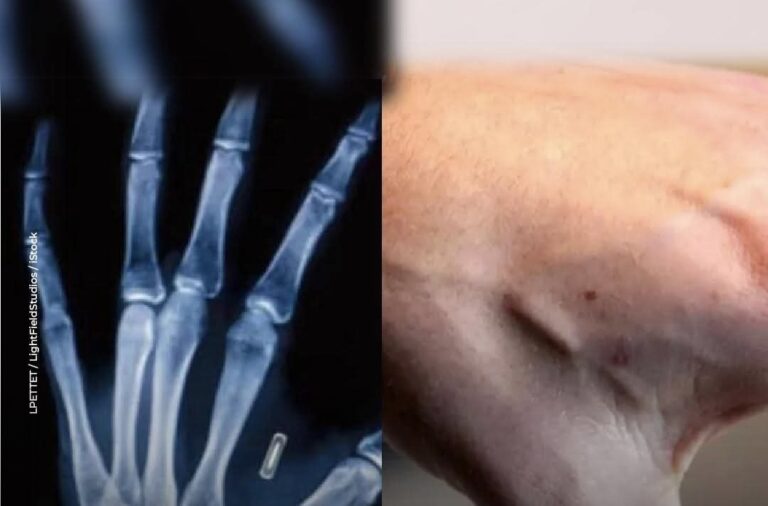

Stockholm, novembre 2025 — En Suède, la technologie s’invite sous la peau. De plus en plus de citoyens optent pour…